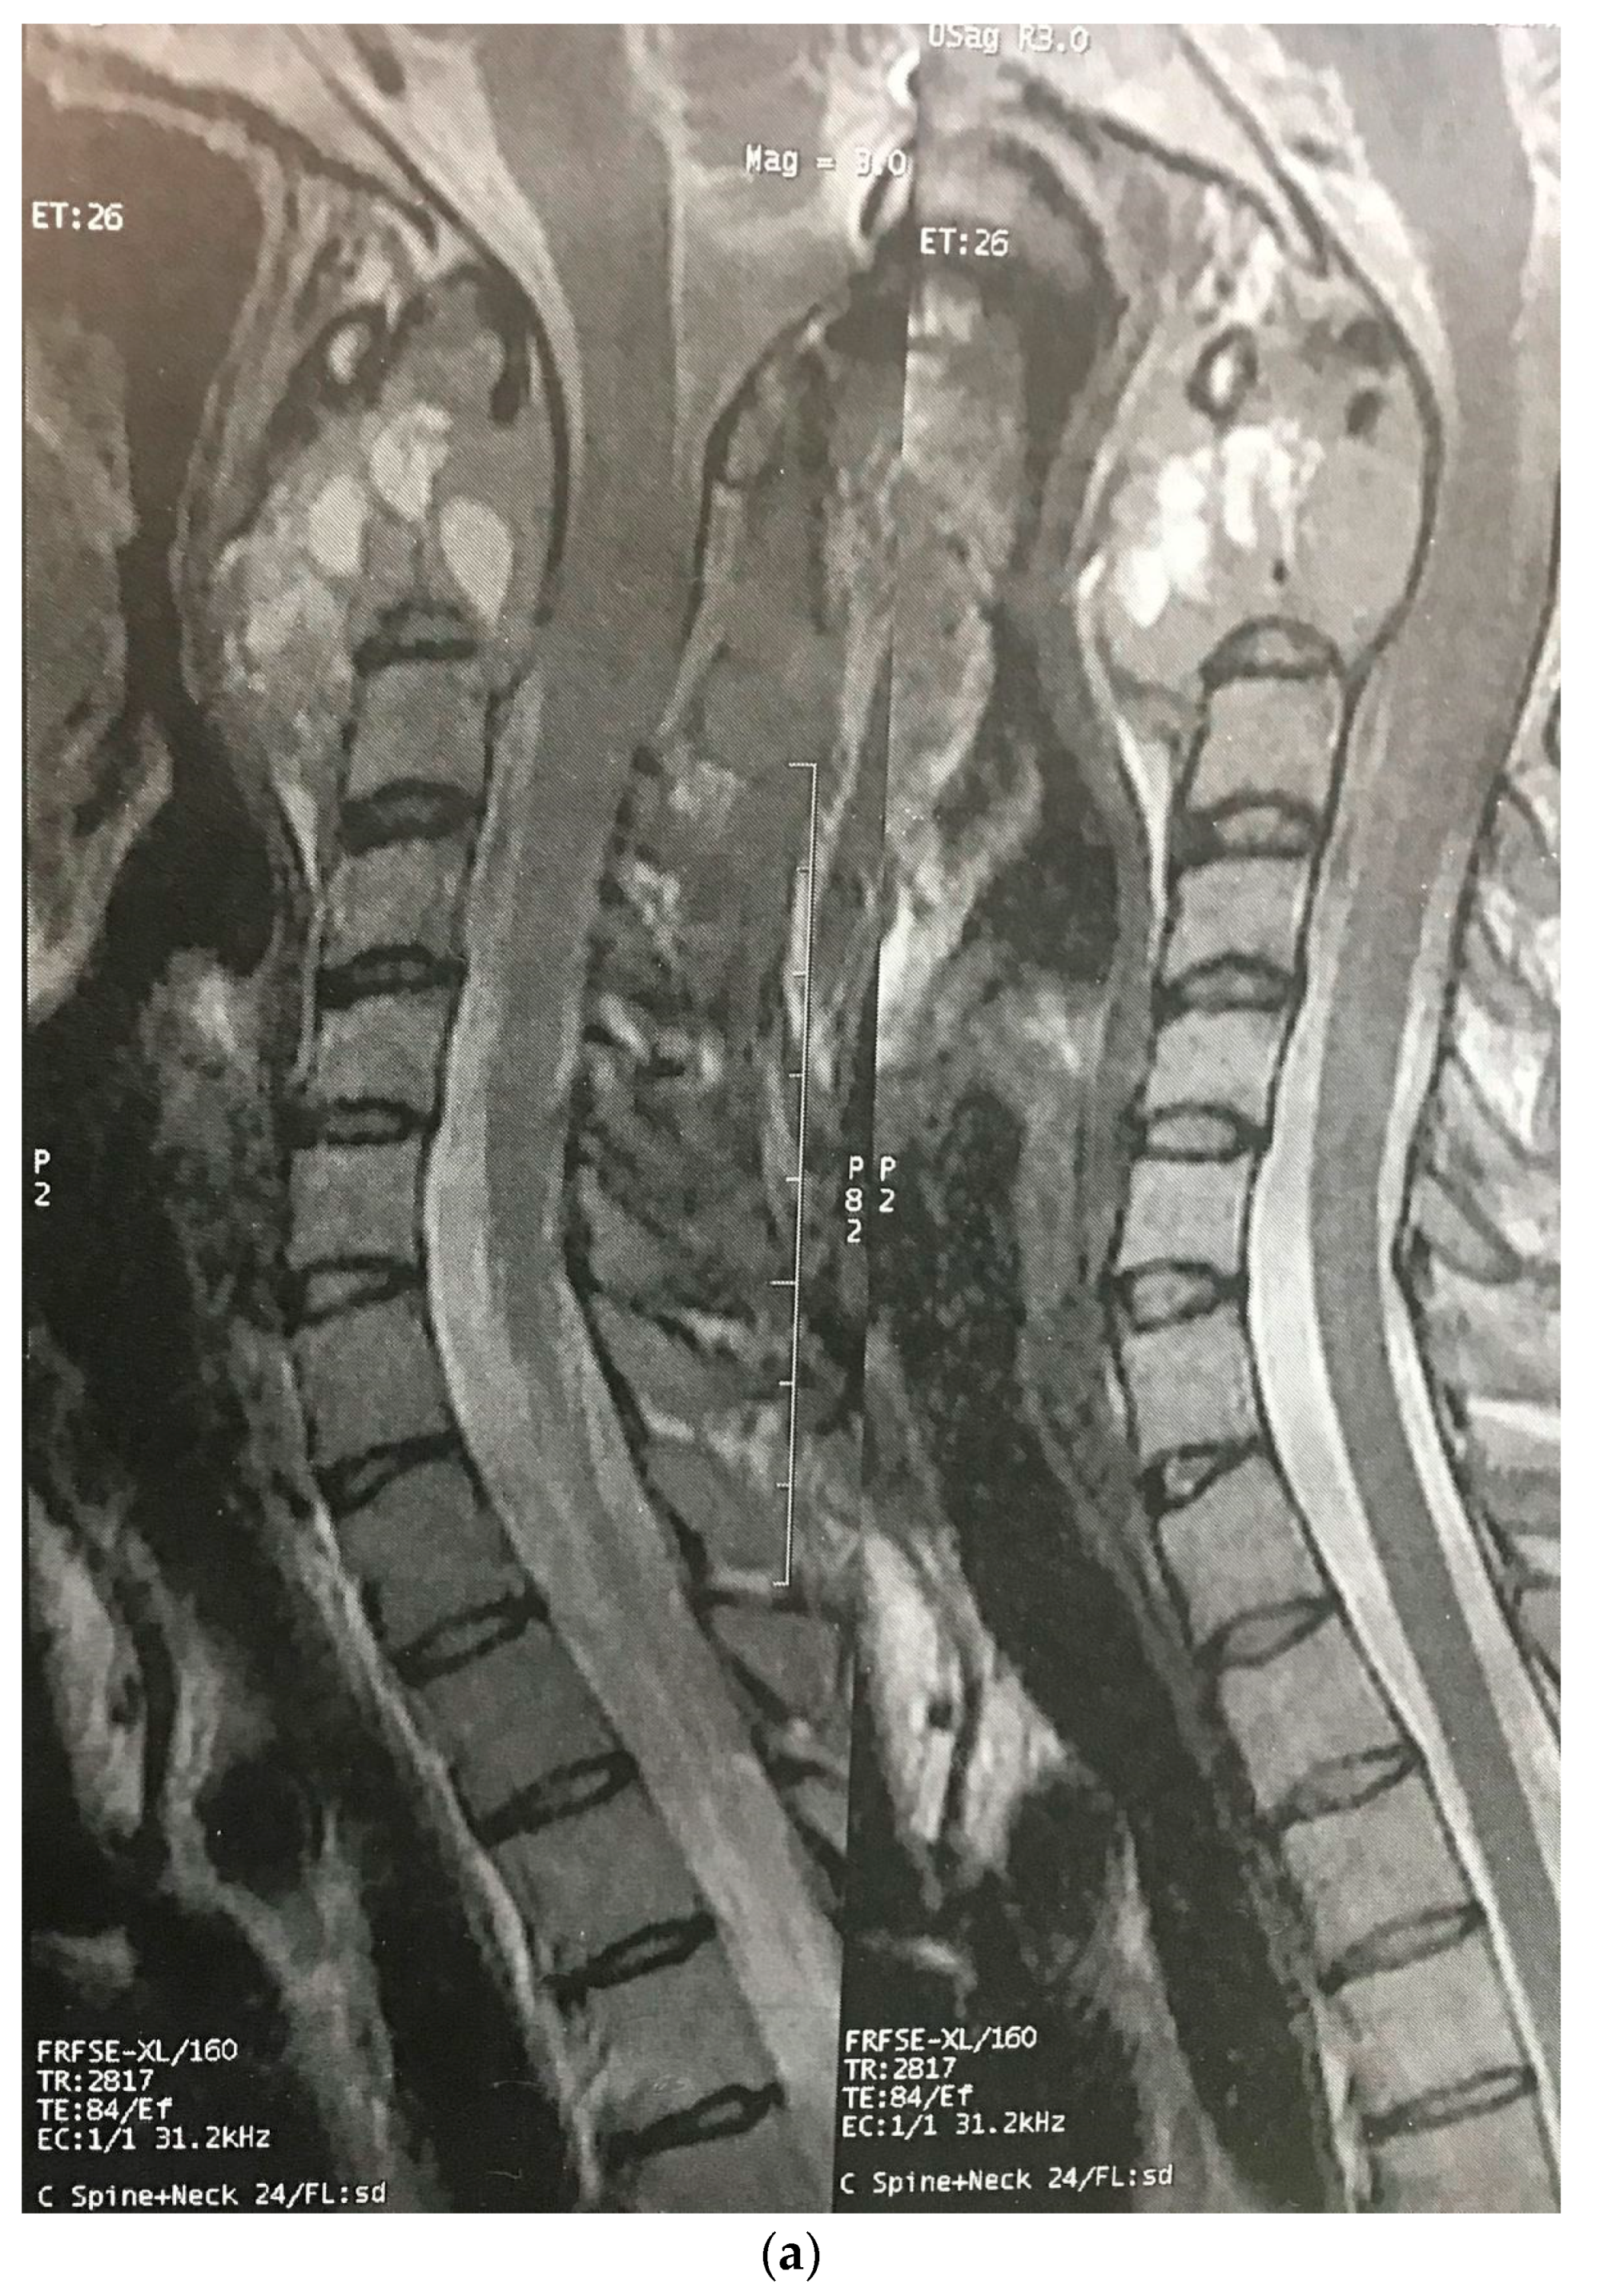

| The current case | 29, female | C2 | CD45, CD43, CD68, S100 | Surgery and radiotherapy | Brain metastasis after 9 months |